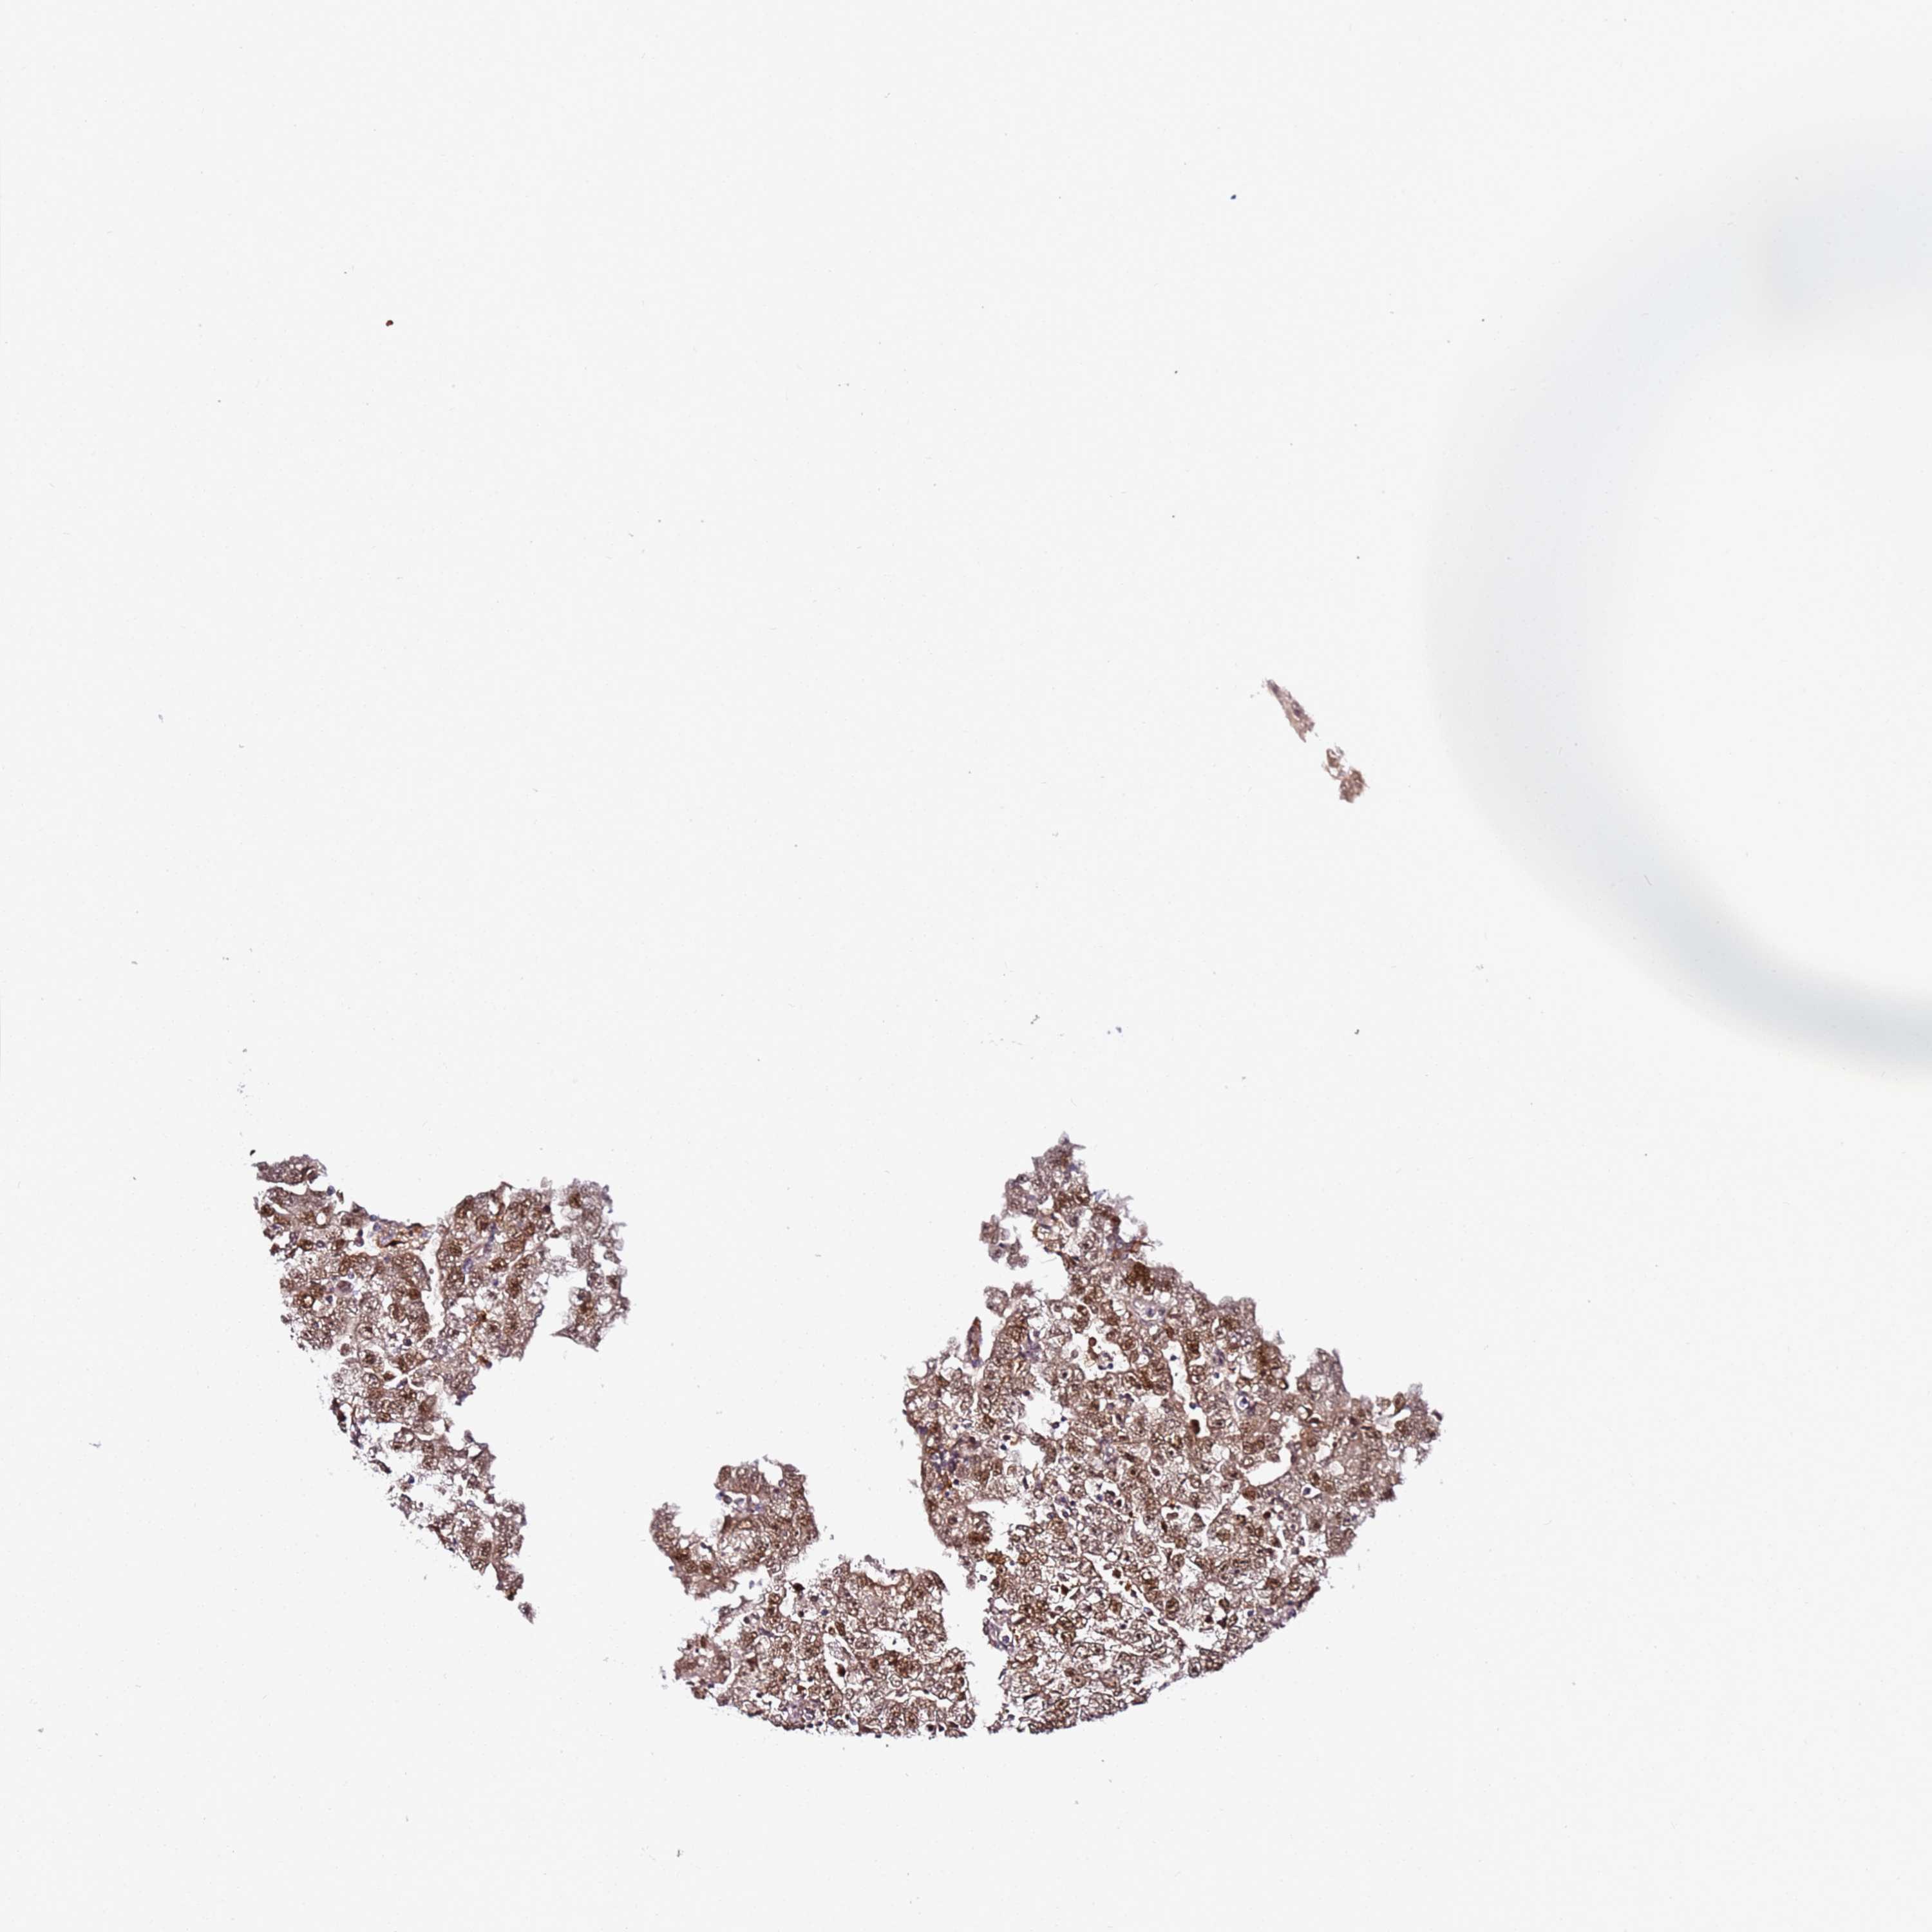

TESTIS CANCER - Protein expressioni

A mouse-over function shows sample information and annotation data. Click on an image to view it in a full screen mode. Samples can be filtered based on level of antibody staining by selecting one or several of the following categories: high, medium, low and not detected. The assay and annotation is described here.

Note that samples used for immunohistochemistry by the Human Protein Atlas do not correspond to samples in the TCGA dataset.

Antibody stainingi

Antibody staining in the annotated cell types in the current human tissue is reported as not detected, low, medium, or high, based on conventional immunohistochemistry profiling in selected tissues. This score is based on the combination of the staining intensity and fraction of stained cells.

Each image is clickable and will lead to virtual microscopy that enables deeper exploration of all samples and also displays staining intensity scores, fraction scores and subcellular localization as well as patient and tissue information for each sample.

Antibody HPA045780

Staining

High

Medium

Low

Not detected

Intensity

Strong

Moderate

Weak

Negative

Quantity

>75%

75%-25%

<25%

None

Location

Nuclear

Cytoplasmic/membranous

Cytoplasmic/membranous,nuclear

Carcinoma, Embryonal, NOS

Seminoma, NOS

Urothelial carcinoma, High grade